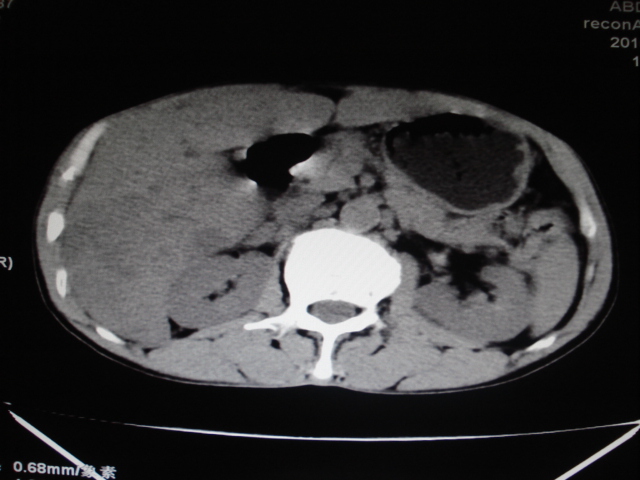

男性,62岁。肝右叶占位,平扫及增强如下,延迟期为15分钟扫描。